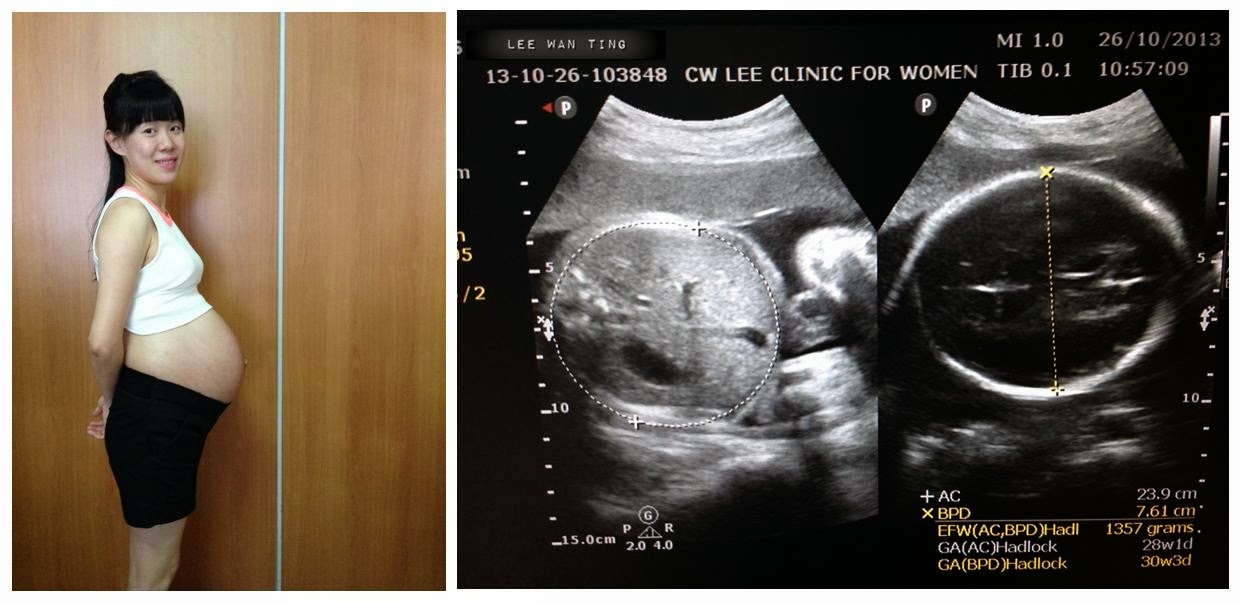

My tenth appointment - *calendar week 28! Yes, officially into 3rd trimester!

Ok, *disclaimer... accordingly to Gynae's calendar, I am at week 28 but based on Baby N's scan, he is currently at week 30 - as you can see from the scanned ultrasound image... Erm, so I should start re-indicate on my blog post title (just in case I lost count again...)!

Baby N's head now measuring 7.61cm and weighs 1357gm! Based on Gyane's advice, baby's weight growth is approx. 200gm per week, so we are kinda on the right track... say by full term (in 37 weeks) yet in another 9 weeks to go, he should weigh around 3157gm (based on ah Thiang's calculation lah...). And yes, hang it there Baby N... we will see you in Jan 2014!!!

Baby bump and scan at *calendar week 28!